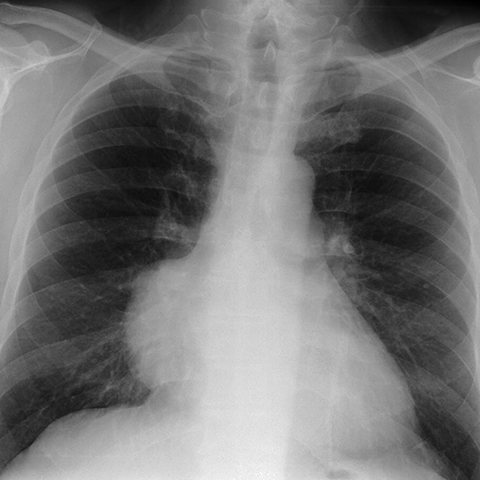

Mediastinal mass, thymoma [1 of 3]